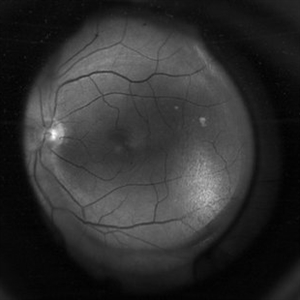

Exudative Retinal Detachment

Oct 26 2024 by rahul saradge

41y/M, k/c/o TYPE 1 DM DOV SINCE 1 WEEK OU H/O TYPHOID 2 WEEKS BACK Here is the image showing Exudative RD in Right Eye We Planned PRP laser for this patient, advised him Carotid Doppler and 2D ECHO

Photographer: Anagha Wakode, Isha Netralaya Thane

Imaging device: optos

Condition/keywords: choroidals, exudative Retinal detachment